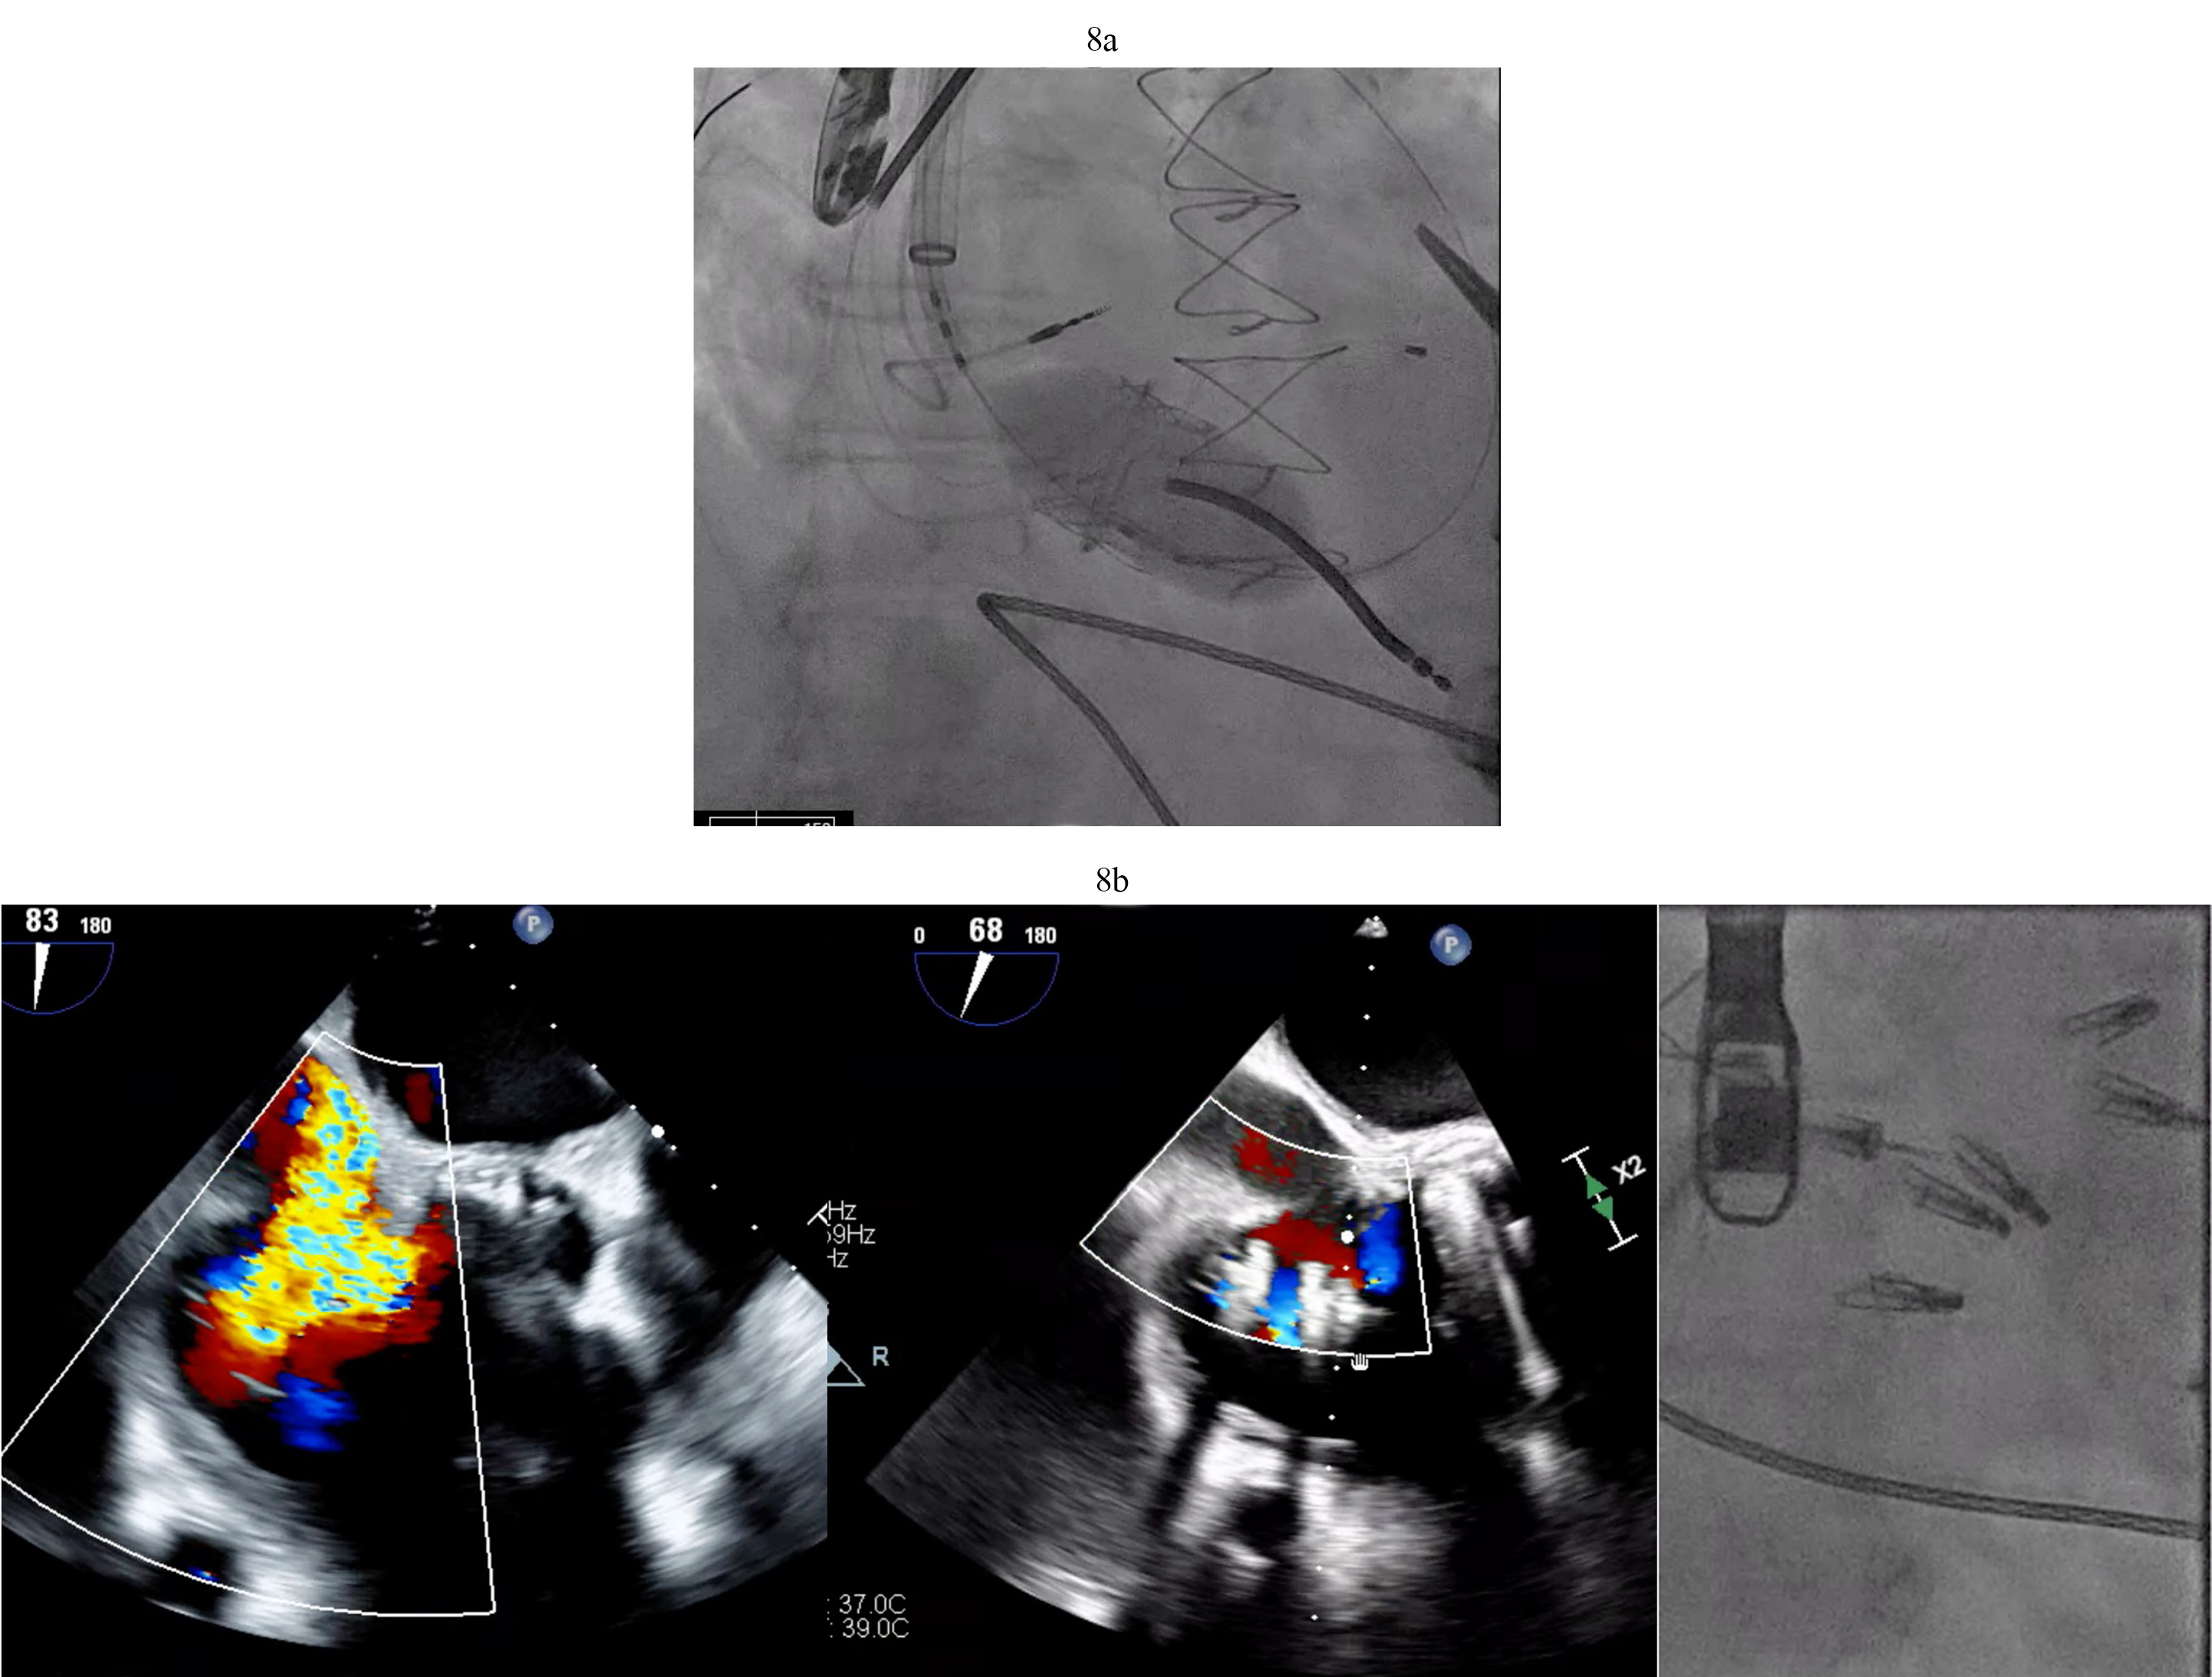

In LVAD patients that have had prior ring annuloplasty repairs and severe tricuspid regurgitation, transcatheter TV replacement is an option utilizing commercially available TAVR valves in a surgical ring approach. Our group successfully performed valve-in-ring TTVR in an LVAD patient with severe TR refractory to medical treatment (Fig. 8a). T-TEER in an LVAD patient (Fig. 8b) has been performed by our group and others [29]. As discussed above CIED leads are present in a large portion of LVAD patients and this approach may not be as successful given the anatomical challenges including large coaptation gaps (

Fig. 8. Tricuspid valve valve-in-ring TTVR in LVAD patient. (a) Sapien 3 valve being deployed in a TV annuloplasty band for treatment of severe TR via trans jugular approach. (b) T-TEER with Triclip. Torrential to mild TR after three Triclips. (Two previously placed Mitraclips are also visible on the fluoroscopy image). T-TEER, tricuspid transcatheter edge to edge repair; TV, tricuspid valve; TR, tricuspid regurgitation.